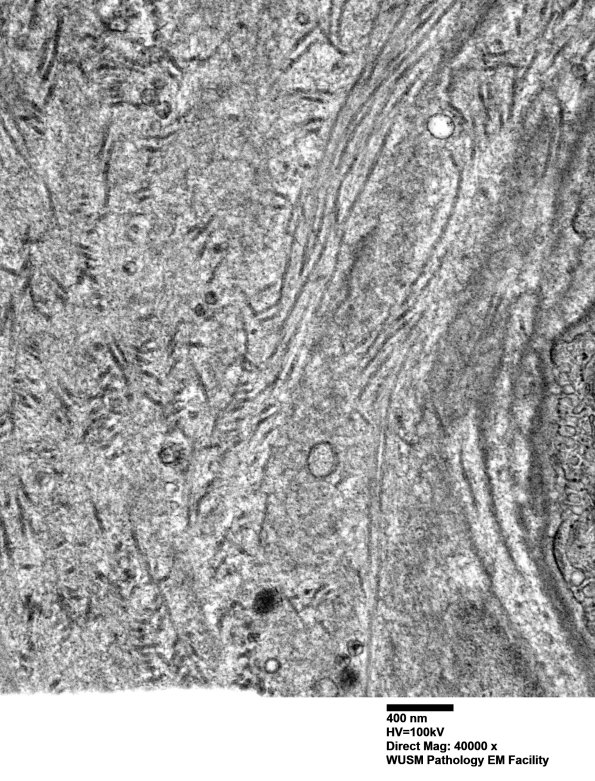

Washington University Experience | VASCULAR | Hypoxia-Ischemia, fetal-neonatal | White Matter | 14B1C (Case 14) EM005 - Copy

14B1C (Case 14) EM005 - Copy